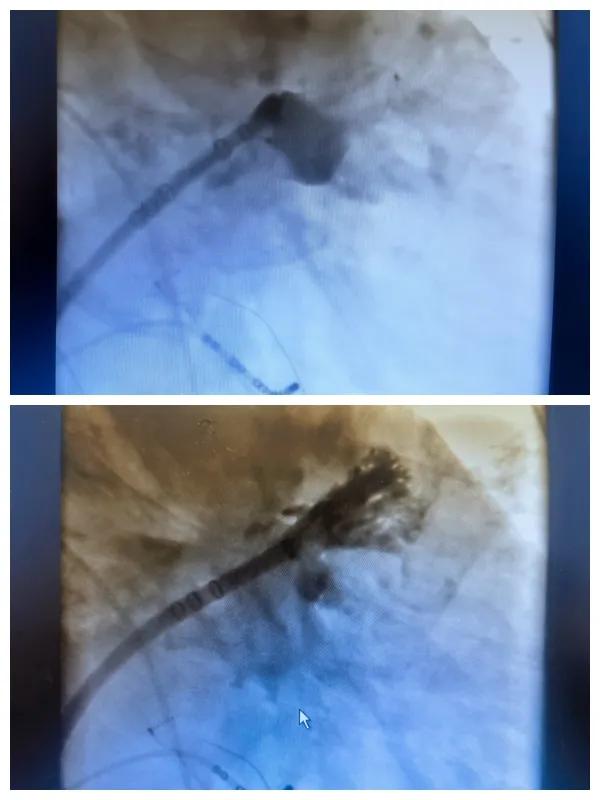

6月26日,市二院成功為一名老年房顫患者實(shí)施了房顫射頻消融術(shù)+左心耳封堵WM FLX一站式介入治療,標(biāo)志著醫(yī)院在心律失常介入治療領(lǐng)域邁出了嶄新的一步,開啟了新的治療篇章。

本次手術(shù)特邀我國著名心血管內(nèi)科專家、河南省胸科醫(yī)院黨委書記袁義強(qiáng)及血管內(nèi)科七病區(qū)主任黃瓊教授蒞臨指導(dǎo),市二院院長王瑾帶領(lǐng)心血管內(nèi)科電生理等專家團(tuán)隊(duì)緊密合作,一次性解決了患者房顫、血栓兩大困擾,也使患者告別了終身服用抗凝藥的痛苦,極大地降低了患者的經(jīng)濟(jì)和用藥負(fù)擔(dān)。

為了讓患者得到全面、綜合的治療,經(jīng)過團(tuán)隊(duì)術(shù)前充分討論,并征得家屬同意,心血管內(nèi)科團(tuán)隊(duì)決定采用目前國內(nèi)外先進(jìn)的房顫射頻消融術(shù)+左心耳封堵WM FLX一站式介入微創(chuàng)手術(shù)來治療老人的疾病。整個(gè)手術(shù)過程圓滿順利,術(shù)后何大爺各項(xiàng)體征正常,蘇醒后順利返回病房。

針對一部分栓塞風(fēng)險(xiǎn)高的病人,但是病人又存在有抗凝藥禁忌的情況下,如何在解決房顫的同時(shí)又預(yù)防栓塞的發(fā)生?一站式手術(shù)應(yīng)運(yùn)而生,通過導(dǎo)管消融將其轉(zhuǎn)成竇性心律,解決或減少病人心衰發(fā)生,另外通過左心耳封堵術(shù),代替終身口服抗凝藥來進(jìn)一步預(yù)防栓塞事件的發(fā)生。